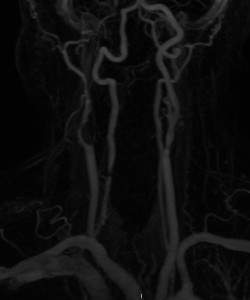

This is the neck MRA of the same patient as above: